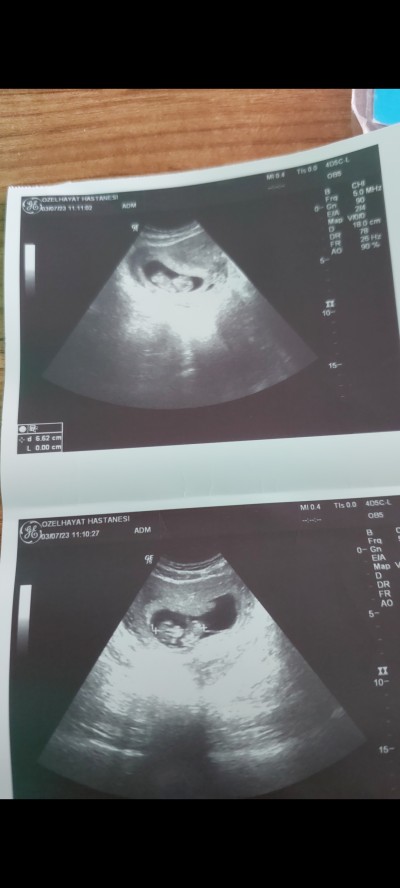

Arkadaşimada cinsiyet tahmini yaparmisiniz :)

10+2 gunluk

Erkek gibimi geldi

Bana da erkek gibi geldi oğlumunda bu haftalarda ultrasyonuna baktım çok benziyor kese tipi falan

Kız doğuyor içime fasulye kese :))

Bende kız diyorum çünkü benim kese yuvarlak bayağı ve erkek dendi :)

Bana da kese yuvarlaksa kız demişlerdi fasülye gibiyse erkek

Erkek bence sağlıkla kucağına almayı nasip etsin Rabbim arkadaşına

Kız bebek......

keseye göre tahmin ettim